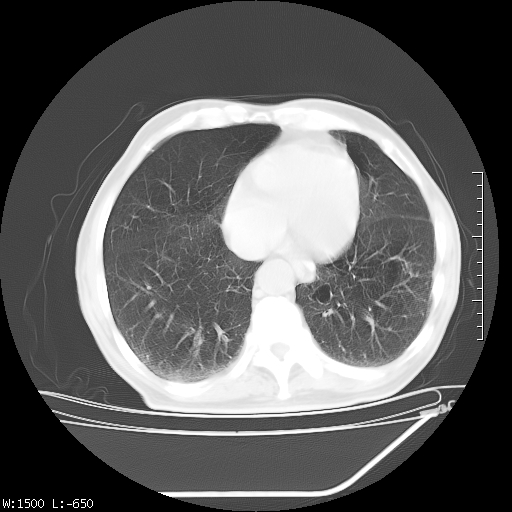

标题: CT23994:男、72、咳嗽、气短两月余,近来消瘦。 [打印本页]

标题: CT23994:男、72、咳嗽、气短两月余,近来消瘦。

tb可能性大(双肺均可见片状密度增高灶,其内可见低密度空洞)。

双肺继发性肺结核

右上肺大片状密度增高影,与胸膜关系密切,内见低密度透亮影,胸膜下可见三角形不张影,左下肺沿支气管走形结节影,纵膈内淋巴结显示。考虑结核并疤痕性不张可能性大,建议穿刺活检,排除肺泡癌。